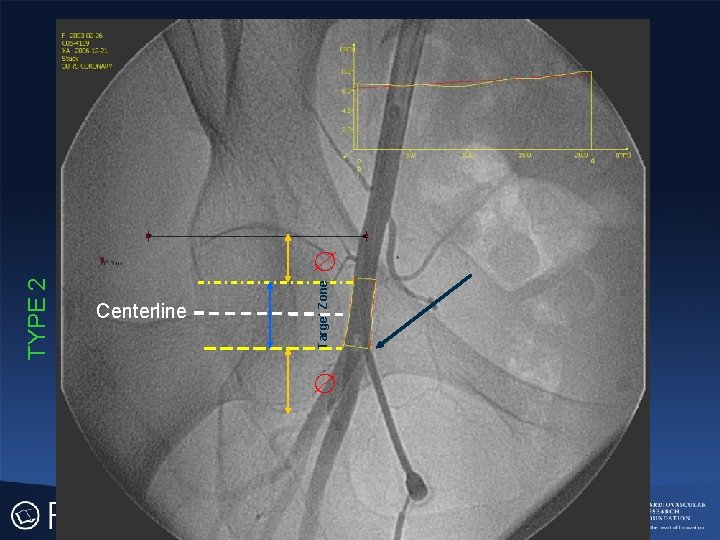

TYPE 2 Centerline Target Zone

Cumulative Probability of Being Outside Target Zone Above FH Centerline Below

IEA FH Centerline Cumulative Target Zone BIF